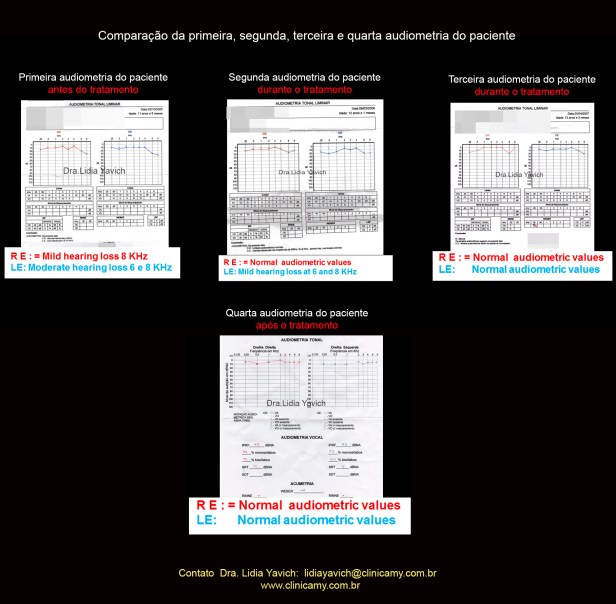

A primeira audiometria do paciente revela uma discreta hipoacusia no ouvido esquerdo e uma leve hipoacusia no ouvido direito.

A segunda audiometria do paciente revela limiares normais no ouvido esquerdo e uma discreta hipoacusia no ouvido direito.

Comparação da primeira e a segunda audiometria do paciente durante o tratamento.

Normalização dos limiares no ouvido direito e melhora nos limiares do ouvido esquerdo.

A terceira audiometria do paciente revela limiares normais no ouvido esquerdo e limiares normais no ouvido direito.

Comparação da primeira, segunda e terceira audiometria do paciente durante o tratamento.

Normalização dos limiares no ouvido direito e normalização dos limiares do ouvido esquerdo.

A quarta audiometria do paciente após a finalização das duas fases do tratamento mantém os limiares normais no ouvido esquerdo e limiares normais no ouvido direito.

Comparação da primeira, segunda, terceira e quarta audiometria do paciente.

Normalização dos limiares no ouvido esquerdo e no ouvido direito.